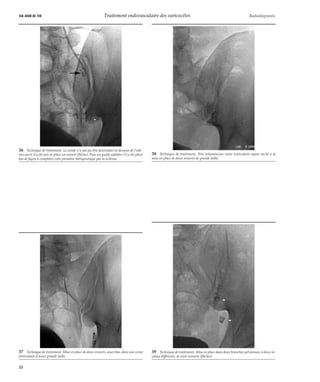

34 Technique de traitement. Après mise en place d’un ressort (2) et injection d’une

première ampoule de sclérosant, la sonde (1) est en partie retirée de façon à scléroser

plus haut le système veineux testiculaire.

32 Technique de traitement. La sonde a été descendue bas en regard de l’épine sciatique.

Le tronc veineux testiculaire sus-jacent n’est pas visible, suite à un spasme sur la sonde.

33 Technique de traitement. Position respective de la sonde et des ressorts (flèche)

après leur largage.

35 Technique de traitement. Il existait deux branches importantes au niveau pelvien,

on a d’abord placé dans la première branche cathétérisée un ressort (flèche) ; puis la

sonde a été descendue bas dans le tronc principal pour la sclérose.